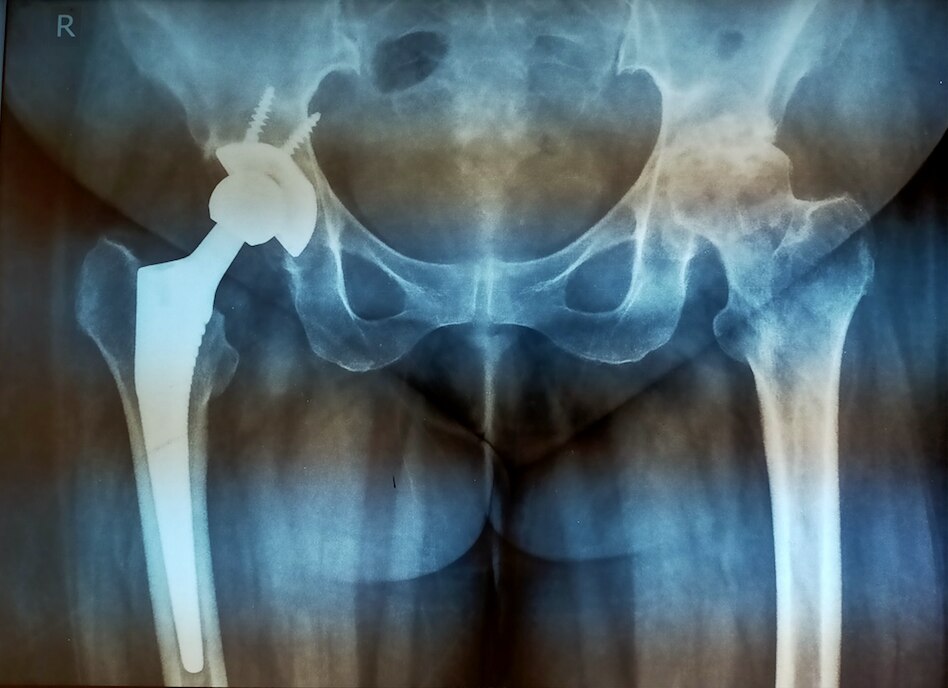

Dr Rahul Rane is an Orthopaedic Surgeon with 16 years of experience in the field of Orthopaedics. He has taken his Master's Degree in Orthopaedic from Mumbai's reputed Lokmanya Tilak Medical College. He has vast experience in treating all kinds of Orthopaedic and Spine problems He is a master in Spine surgery with cutting-edge Endoscopic spine Surgery techniques with no complications. Patients can walk on the same day after endoscopic spine-surgery. He had done Advance Spine Surgery fellowship Training in Korea. He performs all kinds of joint replacement surgeries with excellent results. His operated knee and Hip replacement patients walk full weight bearing after 1 day. His patient's post Surgery walking freely and performing all kinds of work. He is a fitness freak, an avid Marathon runner. He is passionate about making his patients recover faster. “My patient should resume to routine earliest” is his motto.